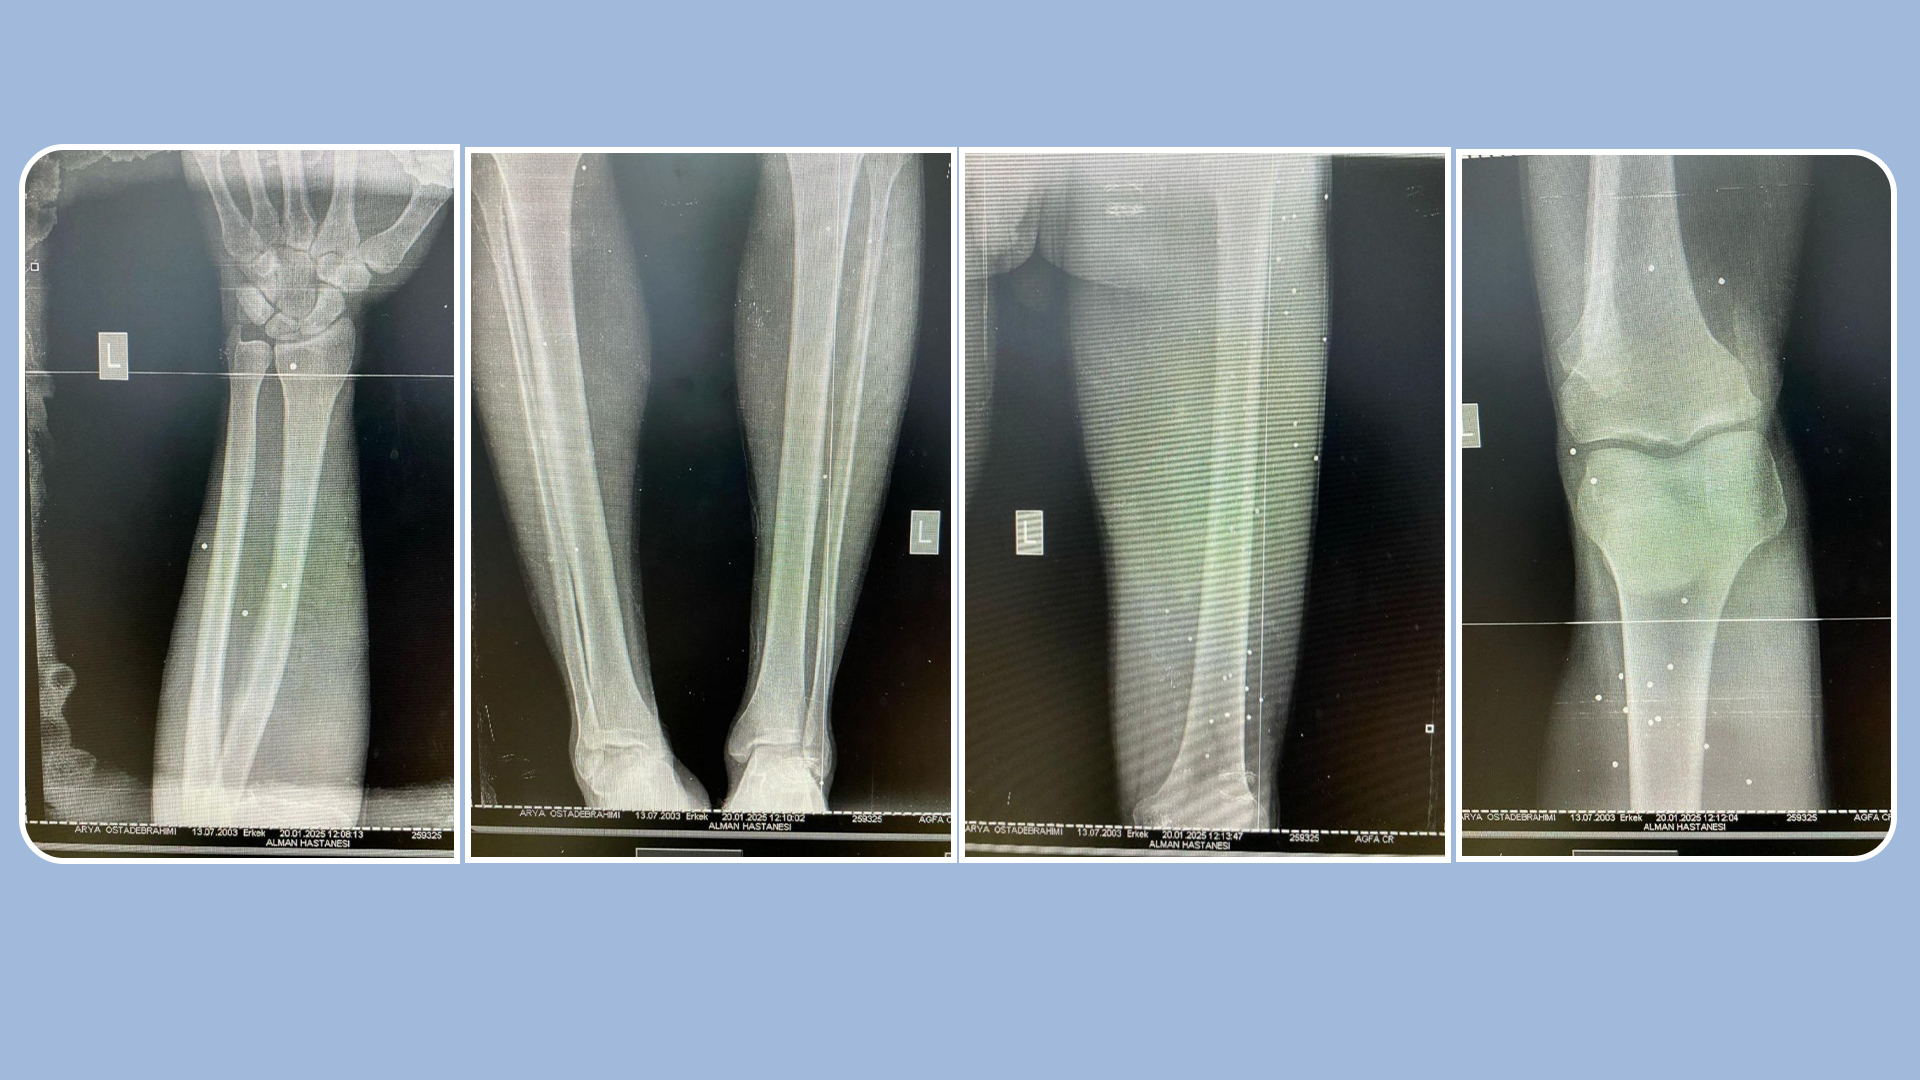

From the shooting of more than a hundred bullets on October 27, the volunteer doctor was able to remove only about 30 pellets from his body. However, more than 80 pellets still remain in his body. The results of medical examinations in Turkey have also confirmed this, stating that many pellets have penetrated deep into the tissues.

As a result of this situation, Arya still struggles with chronic pain. He limps on his left leg because one of the pellets is embedded in the leg bone, and without advanced surgical equipment, it is not possible to remove it. Turkish doctors, after detailed examinations, have warned that surgery to remove the remaining pellets could be very dangerous; because several of them are located in sensitive areas such as around the veins of the left forearm, behind the knee, the bend of the leg, and the left groin.

The lack of advanced surgical facilities and the heavy costs of surgery in Turkey have meant that it has not been possible to remove the pellets so far. Arya says: "The pellets that hit my knees are palpable."

Images of Arya's injury with more than 100 pellet bullets in the October 27, 2022 protests;

CT scan images of the status of the pellets fired into Arya Ostadebrahimi's body;